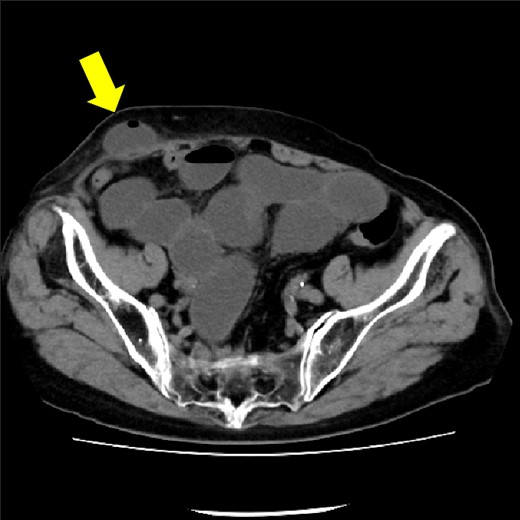

The drain was removed on postoperative day 2. On the night of the third postoperative day, the patient vomited. On the morning of the fourth postoperative day, mild abdominal pain and a ping-pong ball-sized bulge and induration were found near the surgical scar of the 5 mm port where the drain had been placed. CT confirmed an incarcerated small intestine and ileus in the 5 mm port scar where the drain had been placed (Fig. 2). Ileus removal was performed on the same day. First, the dilated wound for nephrectomy was opened, and the inside of the abdominal cavity was observed. A hanging small intestine was observed just below the 5 mm port (Fig. 3). Since it could not be conquered manually, a 2 cm vertical incision was made on the 5 mm port wound. The small intestine penetrated the anterior layer of the rectus abdominis muscle, so the fascia was carefully incised to avoid damaging the small intestine. The small intestine was returned to the abdominal cavity. The small intestine was slightly discolored (Fig. 4), but after discussion with the gastrointestinal surgeon, it was determined that it was not necrotic. No small intestine resection was performed. The wound was carefully closed using fascial sutures to prevent recurrence. The fascia was weak, likely because this patient was taking steroids. The ileus has not recurred since then. The pathological results indicated a maximum diameter of 30 mm, consistent with papillary renal cell carcinoma, classified as pT1a G3 > G2, with negative margins.

Small intestine incarcerated in the fascia of rectus abdominis.